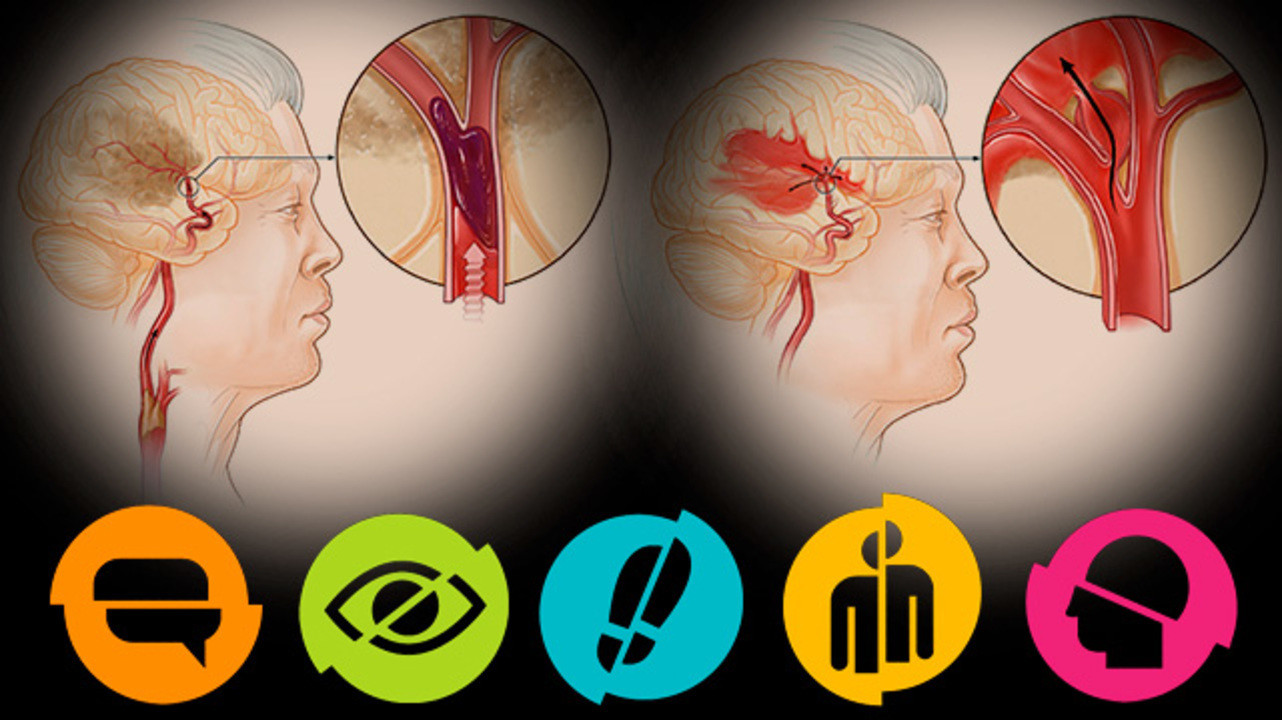

Ишемический инсульт левой стороны: симптомы и реабилитация